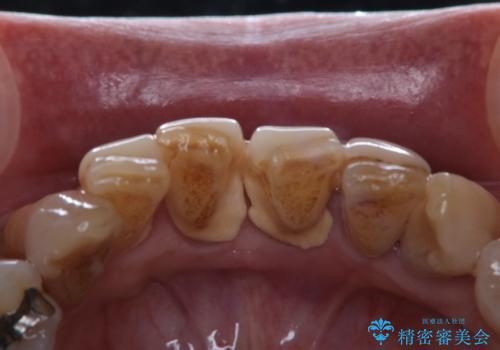

インビザラインでの矯正前にPMTC

- これからインビザラインでの矯正治療が開始する方です。定期的にクリーニングを行っていきたいとのことでした。PMTC30分コースを行いました。

プラーク(細菌の塊)や歯石がたまると歯の表面はザラつきいてきます。そのザラつきは歯周病や虫歯菌の棲家となります。そのまま放置すると、歯肉が腫れてきたり、歯肉から出血したり、口臭が強くでたりします。とくに歯肉の境目は、歯磨きで汚れを除去することが難しく、プラーク(細菌の塊)や歯石が溜まりやすい場所です。

歯並が、がたついている場合はなおさら汚れが溜まりやすいです。矯正治療前や矯正中、定期的にPMTCをすることで、矯正治療中の歯肉トラブルを防ぐことにつながります。